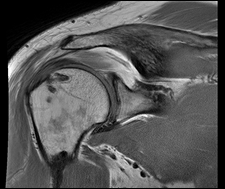

Despite significantly older patients, BioEnthesis showed fewer retears and significantly better MRIs.

INOVA Patient Set

Set of 2 patients out of the Northern Virginia area with postoperative scores and MRIs